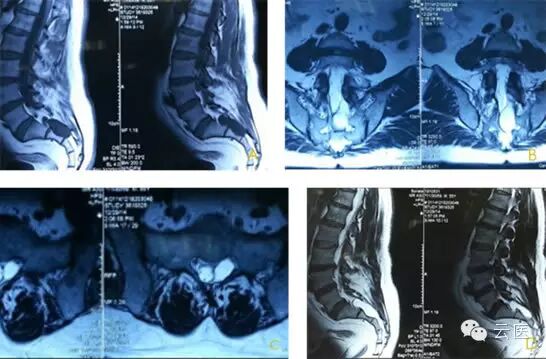

1、复杂症状的骶管囊肿

女,35岁,间断发作性下腹会阴双下肢疼痛8年,近两月加重,床上翻身,迈步走道剧烈疼痛。不能睡觉,不能站立,只能窝在轮椅里,靠止痛药度日。查体除右侧鞍区针刺痛觉敏感,余无特殊,病例详情请至云医#病例讨论#版块查看。

2、骶管病变

男,55岁,左侧腰臀部疼痛5年,渐加重,伴会阴部坠胀不适,久坐久站明显,病例详情请至云医#病例讨论#版块查看。